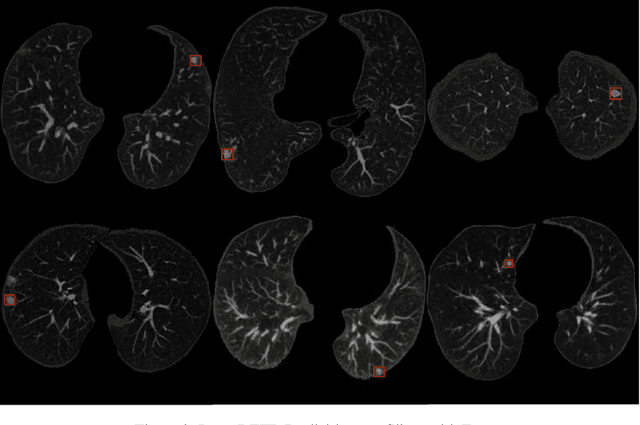

Lung-DETR: Deformable Detection Transformer for Sparse Lung Nodule Anomaly Detection

Figure 3 for Lung-DETR: Deformable Detection Transformer for Sparse Lung Nodule Anomaly Detection